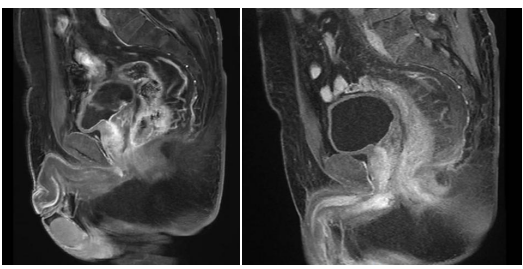

医院购入设备怎么记特别“费”医生的4号机放疗——记腹部放疗一病区MRI-linac Unity临床应用_https://www.jmylbn.com_新闻资讯_第2张

新辅助治疗前后疗效对比